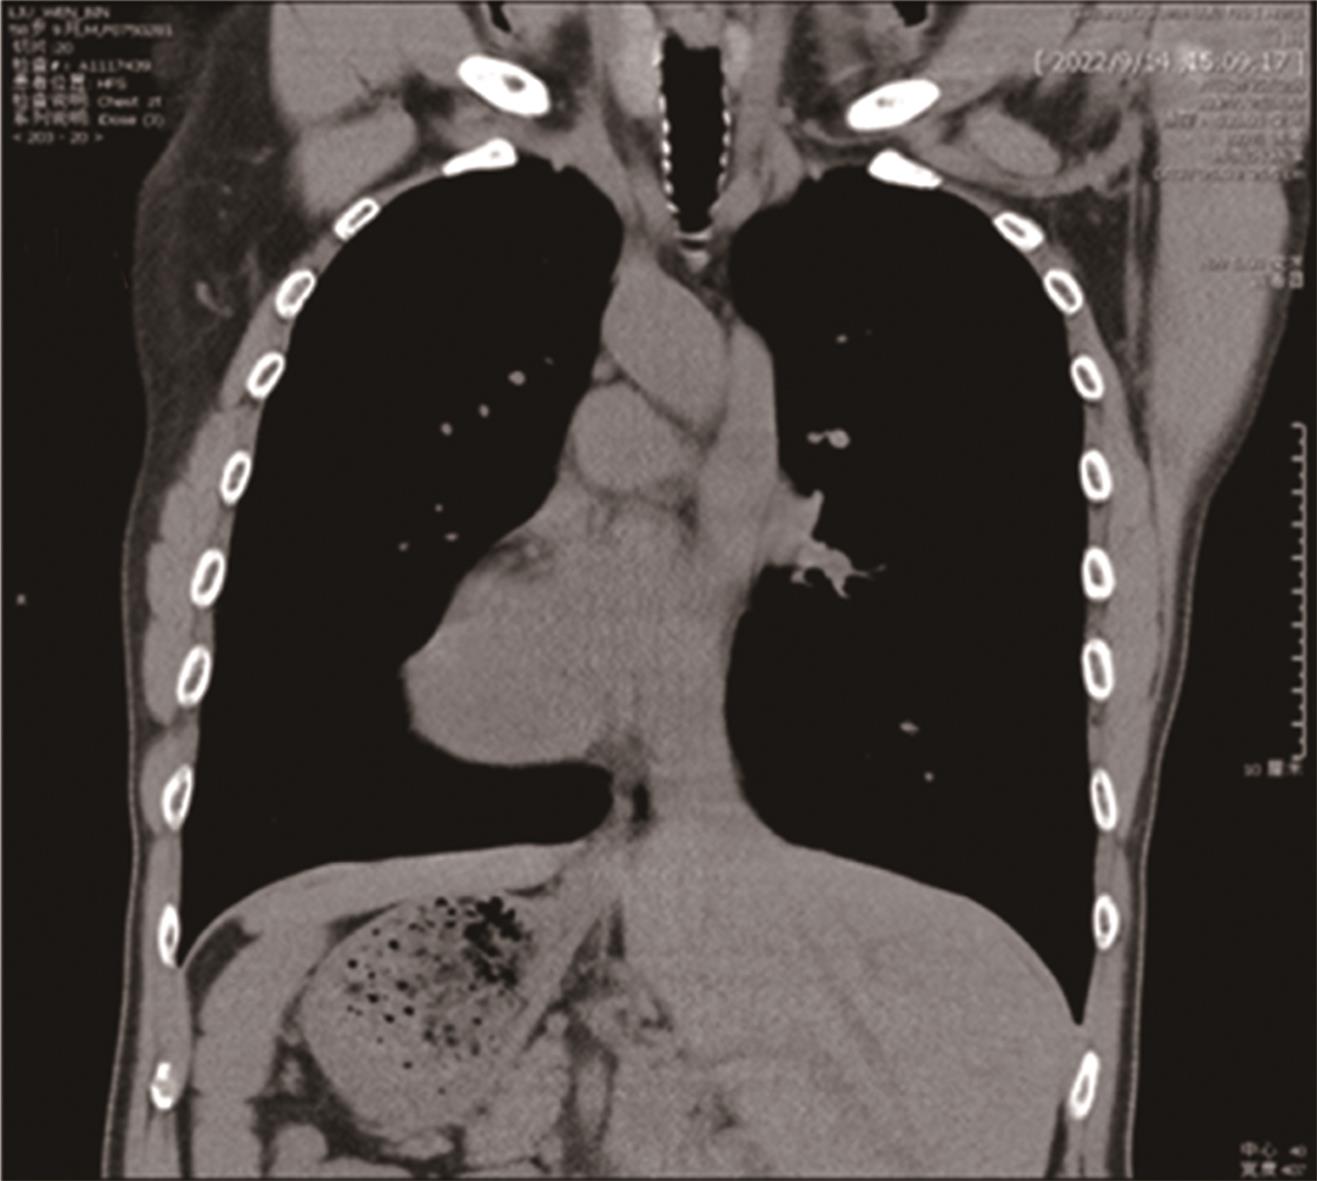

• “镜面人”保留左结肠动脉腹腔镜低位直肠癌根治术1例

2023, 48(7):853-856. DOI: 10.13406/j.cnki.cyxb.003278

摘要 (87) HTML (56) PDF 3.64 M (283) 评论 (0) 收藏